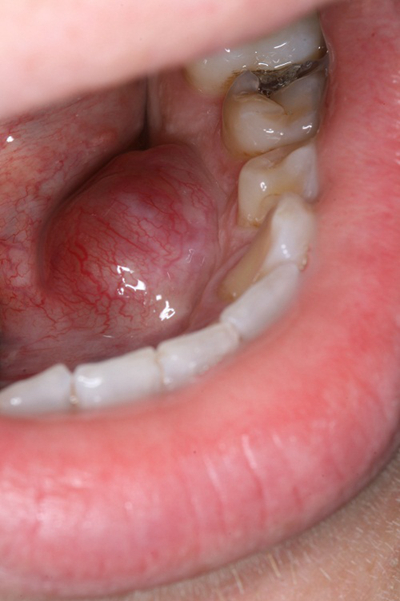

口腔癌圖片

口腔癌的前兆 (8)